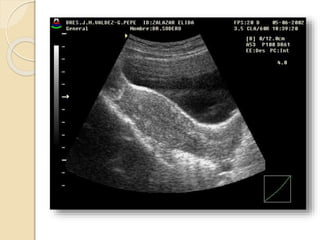

Quistes Endometrósicos:

Clínicamente se manifiesta por dismenorrea,

dispareunia e infertilidad.

La lesion mas detectable por la imágenes esta

constituida por los quistes endometrosicós

(endometriomas) que se forman a partir de los

implantes ováricos configurando los quistes

“achocolatados”.

Se observan quistes de paredes relativamente

gruesas e irregulares con débiles ecos en su

interior debido al contenido hemático.